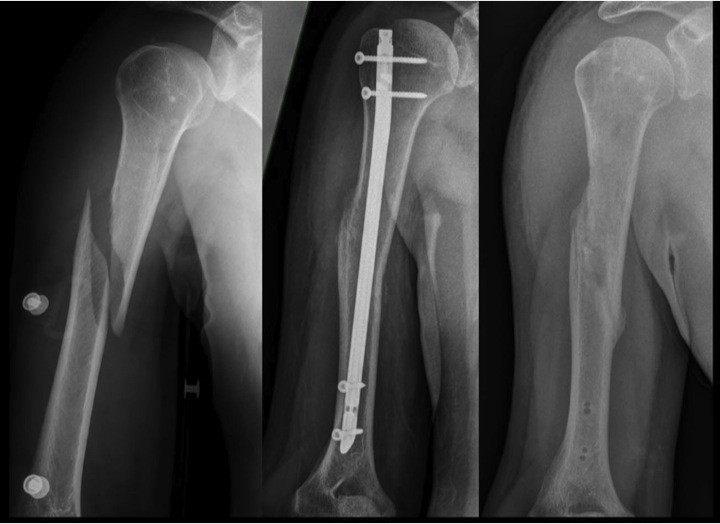

Da hieß es bei beiden, es sei sehr risikoreich und die Schmerzen könnten noch weggehen Der arm wurde operiert mit Nägeln und Platten (weiß nicht genau) Ich habe seit dem ersten Tag nach der Op Physio und das 2-3 mal die Woche

Source: nextmarfpj.pages.dev Operationen von Knochenmetastasen Zentrum für chirurgische MetastasenTherapie , Oberarmbruch - Das müssen Sie jetzt wissen! Allgemein Symptome Schmerzen bei einem Oberarmbruch Ursachen Therapie Operation eines Oberarmbruchs Wann ist eine Operation nötig? Welche Möglichkeiten der OP gibt es (Platte/Nagel)? Dauer Dauer der gesamten Behandlung Dauer der Heilung Dauer der Heilung beim Kind Dauer der OP Dauer des Gipses. Der arm wurde operiert mit Nägeln und Platten (weiß nicht genau).

OBERARMBRUCH . Wir bevorzugen bei komplizierten Brüchen die Stabilisierung mit einer Platte Einige Knochenbrüche des Arms werden mit einer Operation behandelt, bei der Material zur Stabilisierung wie Schrauben und Platte, Draht oder Nagel eingesetzt wird